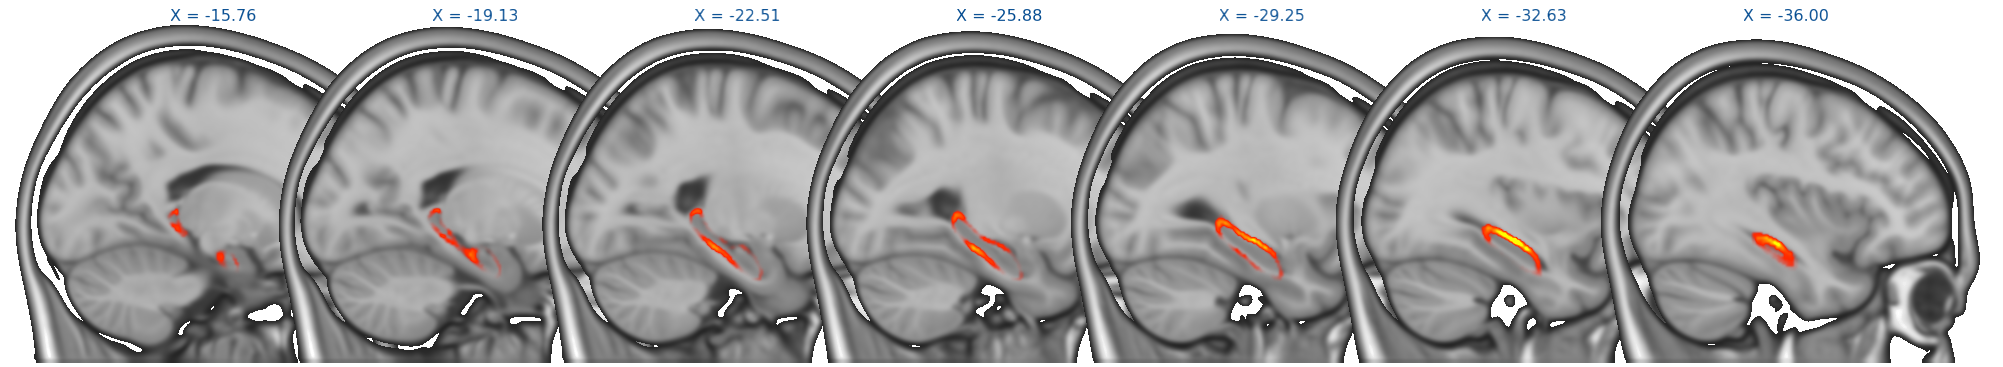

Results from randomise can be viewed in the standard orthographic or lightbox views in FSLeyes. To distinguish the direction of the changes see the description in the section on randomise above.

Viewing results in 2D

A useful option when displaying statistical results is to view the statistic image (e.g. the f-statistic, t-statistic image, etc), and to highlight significant regions with the corrected P-value image. This can be accomplished in FSLeyes like so:

- Start up FSLeyes, and add the following as overlays, ensuring that they are ordered in this way in the overlay list:

- the corrected P value image, e.g.

con1_dis2_L_Hipp_rand_clustere_corrp_fstat1.nii.gz - the statistic image that you want to visualise, e.g.

con1_dis2_L_Hipp_rand_fstat1.nii.gzto display the F-statistics from therandomisecall above. - The MNI152 1mm standard template

- Open the overlay display dialog (the gear button at top-left).

- Select the P-value image in the overlay list, and in the overlay display dialog change these settings:

- Overlay data type to 3D/4D mask image

- Show outline only selected

- Select the statistic image in the overlay list, and in the overlay display dialog adjust the display settings as desired - for example, you can set up a red/blue positive/negative colour display suitable for many statistic values with the following settings:

- -ve colour map selected

- First colour map set to Red-Yellow

- Second colour map set to Blue-Light blue

- Modulate alpha by intensity selected - this causes regions with a low value to be made transparent

- Display range and Modulate range adjusted as desired